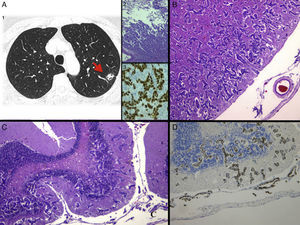

Presentamos un caso poco habitual en una paciente no fumadora de 54 años portadora de un adenocarcinoma pulmonar (fig. 1A) avanzado EGFR mutado, una deleción en el exón 19 (del19), con buena tolerancia y respuesta parcial radiológica tras 6 meses de tratamiento dirigido con erlotinib, un inhibidor tirosina quinasa (ITK) oral.

A) 1: TAC de tórax al diagnóstico, donde se objetiva un nódulo en lóbulo superior izquierdo sugerente de primario pulmonar; 2: imagen histológica con tinción de hematoxilina-eosina (H&E) de la biopsia del nódulo pulmonar, siendo compatible con adenocarcinoma (×4), y 3: tinción de inmunohistoquímica positiva de thyroid transcription factor 1 (TTF-1), que confirma el origen primario pulmonar. B) Imagen histológica con tinción de H&E de la CM con extensa invasión en profundidad de la corteza frontal (×2,5) y C) cerebelo (×4). D) Tinción positiva de TTF-1, confirmando la infiltración por un adenocarcinoma de origen pulmonar.

La autopsia reveló una extensa progresión en forma de carcinomatosis meníngea, con una llamativa invasión en profundidad de todo el parénquima del neuro-eje cerebral (fig. 1A), cerebelar (fig. 1B) y medular, por un adenocarcinoma pulmonar (fig. 1D), con una apariencia macroscópica normal. Curiosamente, no se objetivó enfermedad extracráneo-espinal. El estudio molecular mostró la misma mutación de EGFR que al diagnóstico, del19, sensible a tratamiento con ITK y la mutación T790M, de resistencia adquirida al tratamiento con ITK4, fue negativa.